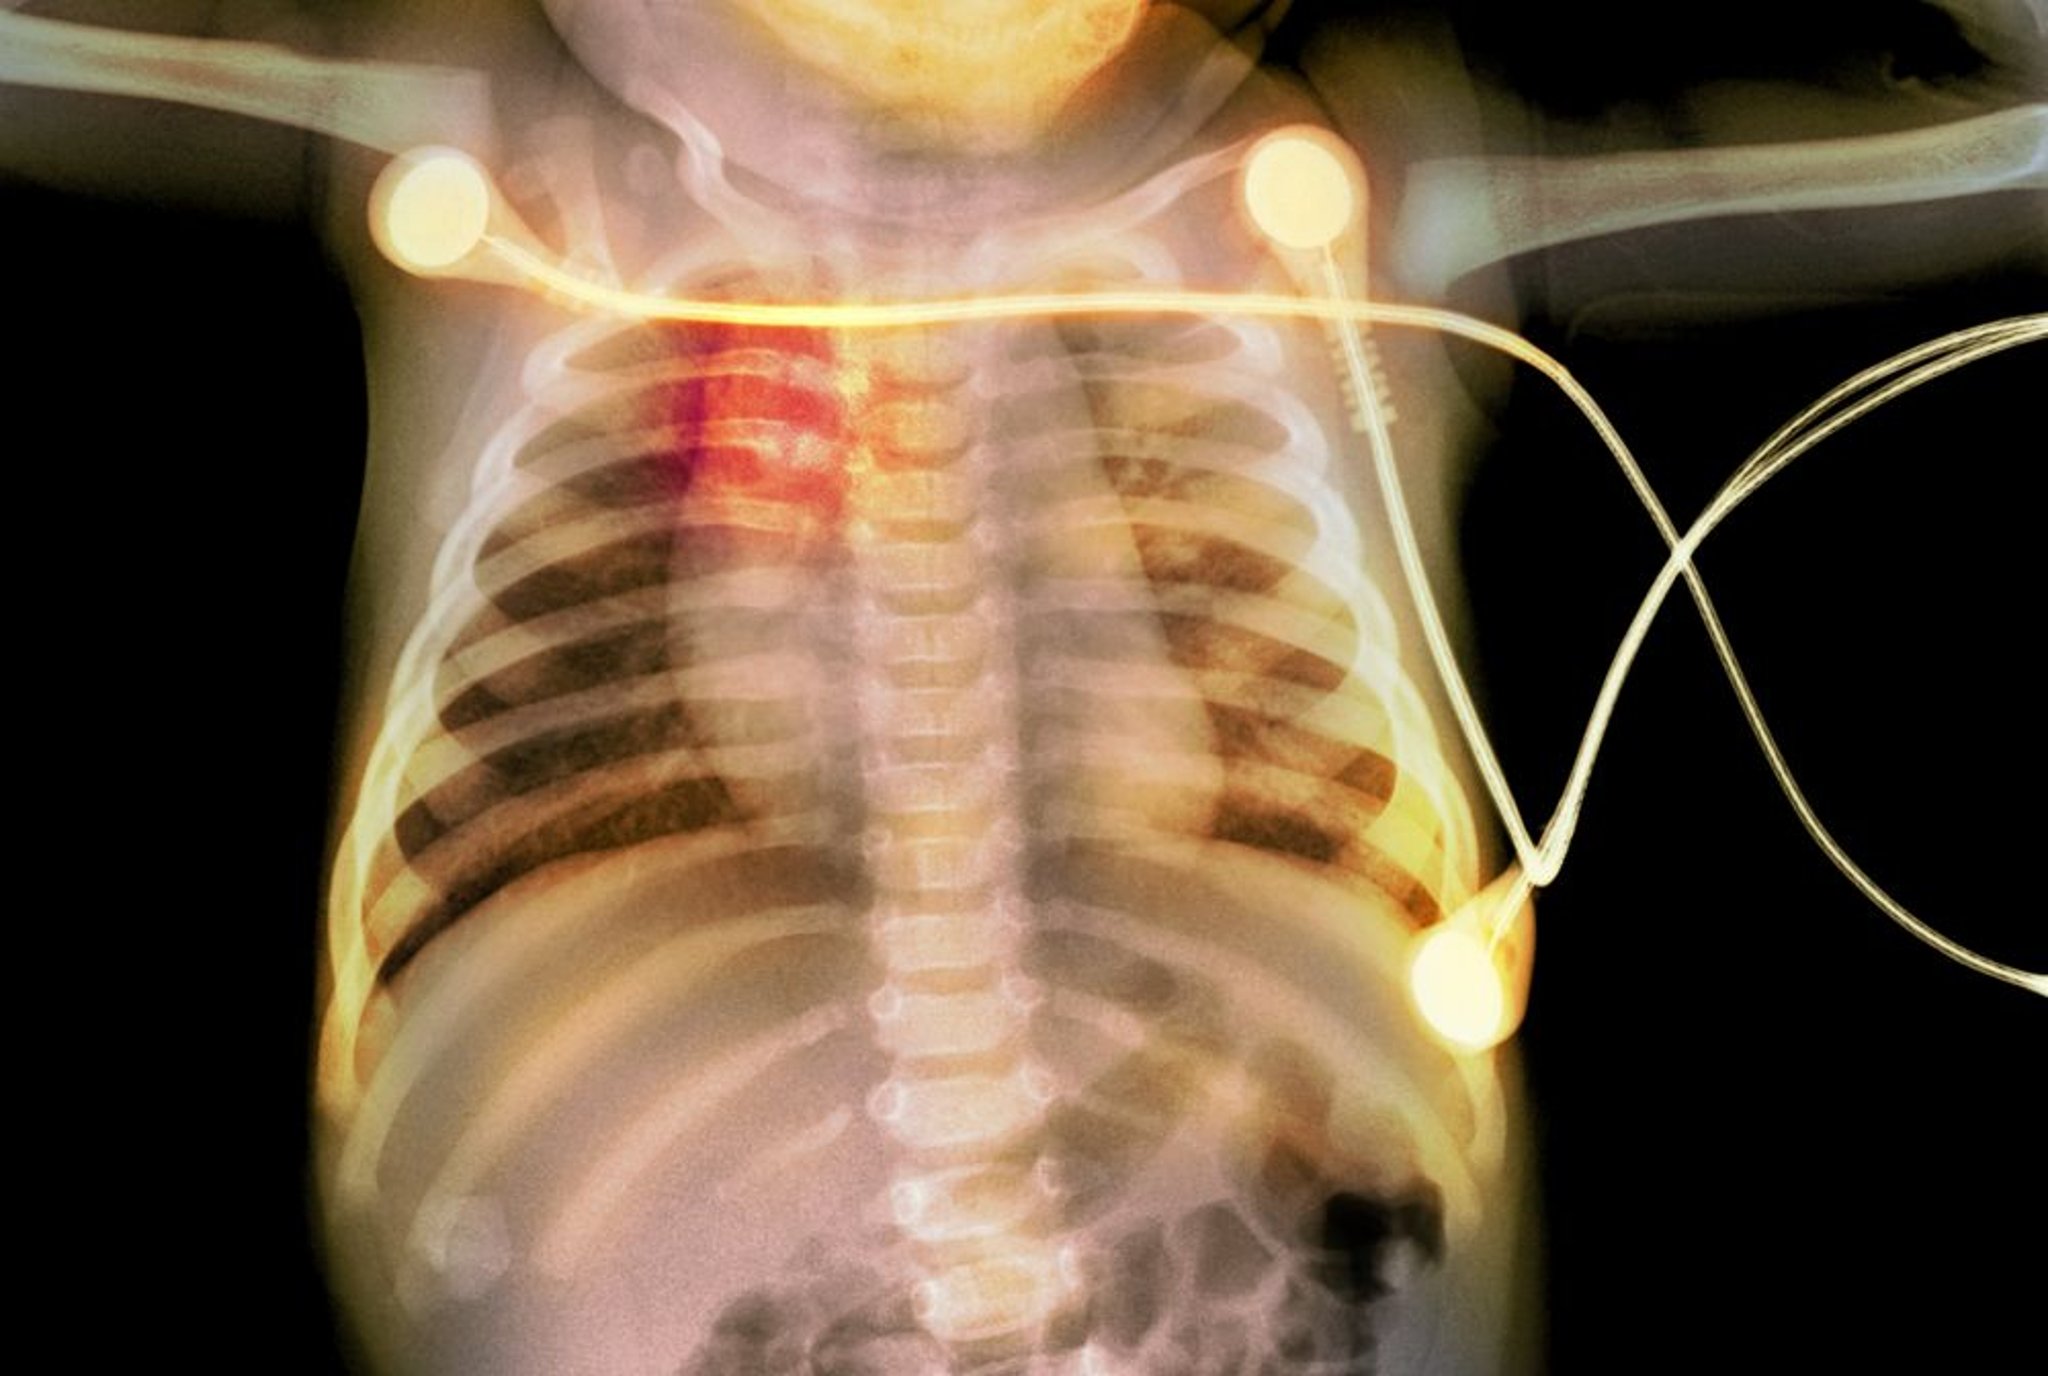

كسور في أضلاع القفص الصدري عند طفل

تُظهر هذه الصورة الشعاعية كسور ضلعية عند طفل (المُشار إليها باللون الأحمر) والتي تقترح تعرض الطفل للعنف.